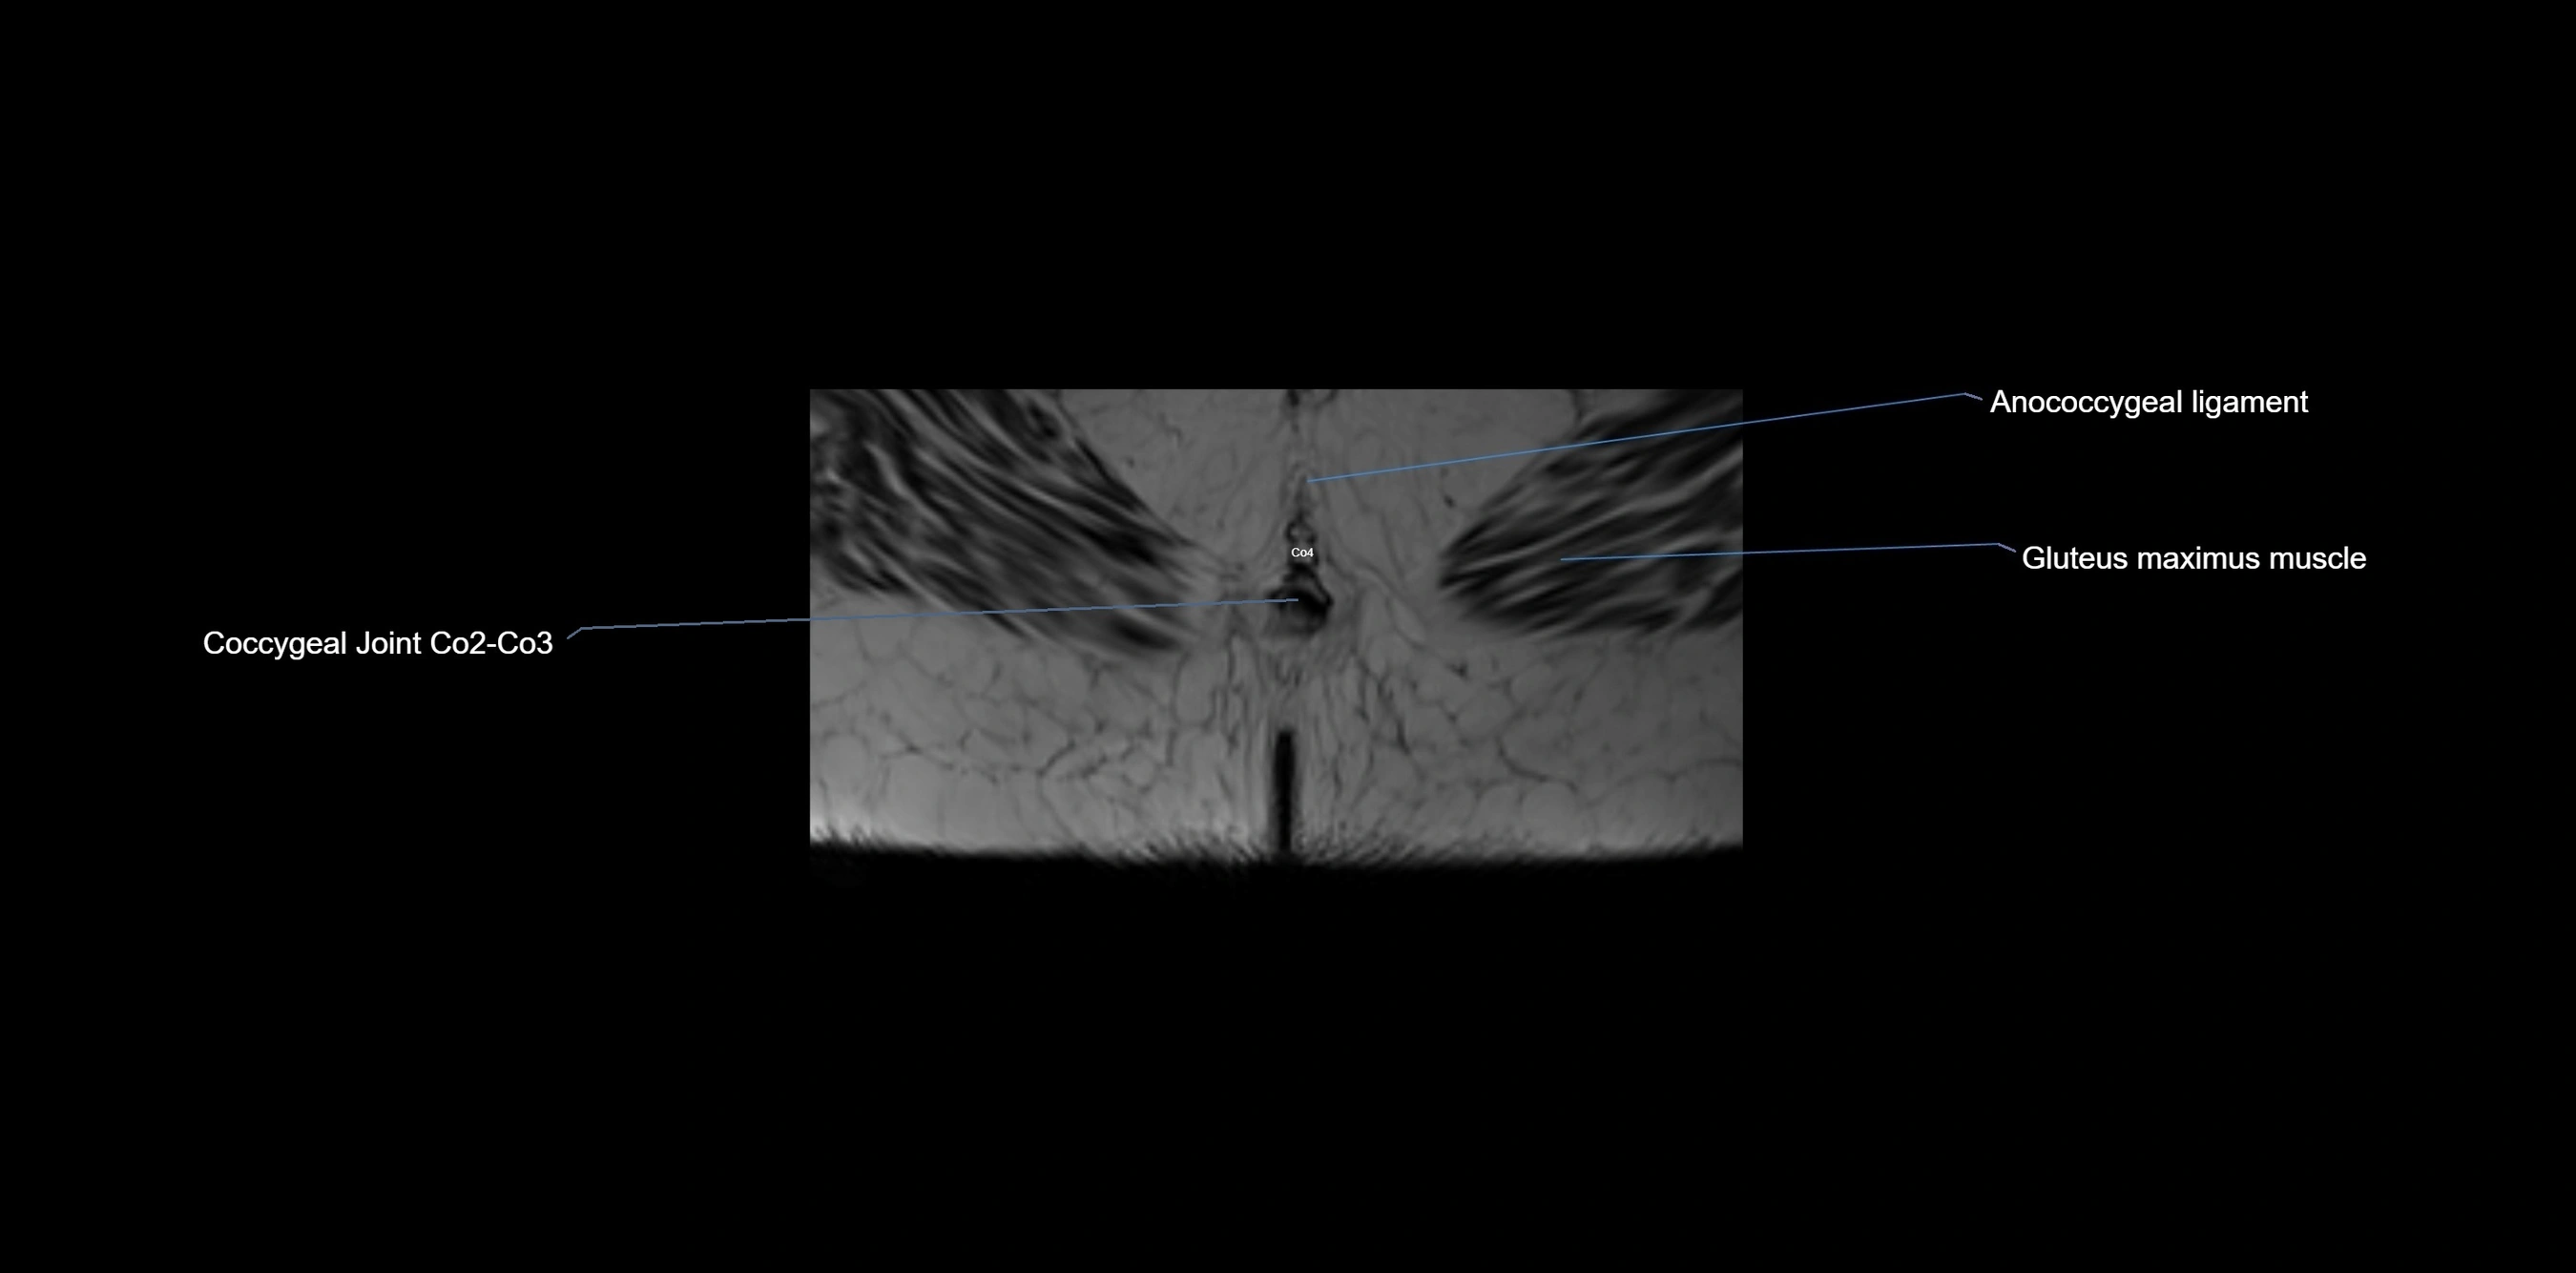

MRI image

image